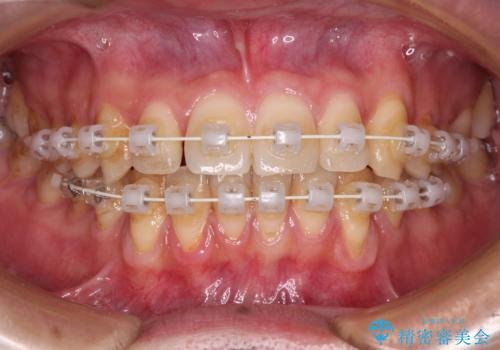

ワイヤー装置での上下前歯の部分矯正

- 矯正装置

- 審美装置

- 上下前歯のデコボコを気にして来院された患者様です。

口元の突出感や奥歯の咬み合わせに問題がなかったため、インビザラインの廉価版パッケージを用いるか上下ワイヤー装置での部分矯正を提案しました。

インビザライン廉価版パッケージの方が価格としては安価でしたが、日々の自己管理が煩雑であるとのことで、ワイヤー装置にて矯正治療を行うこととしました。

部分矯正は咬み合わせが不安定になったり、スペースができてしまったりと、適用となる患者様は極めて限られますが、こちらの方はスムーズに治療を終えることができました。